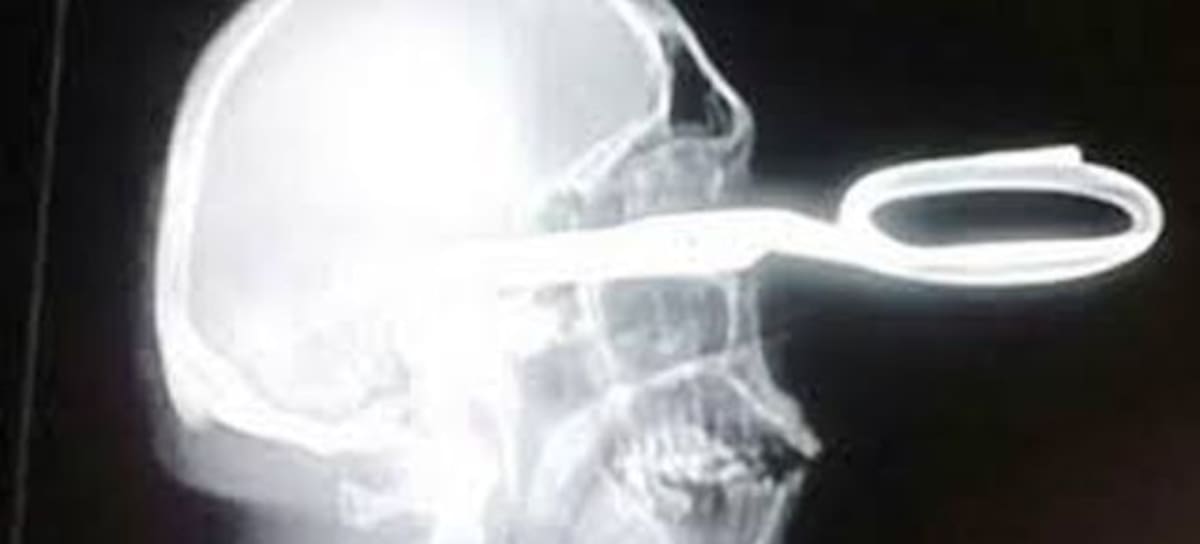

Tijera de 18 cm clavada en su ojo

Las tomas de rayos X confirmaron que Jonas había sido apuñalado en el lado superior izquierdo de su cráneo y las tijeras había penetrado en su lóbulo parietal del cerebro. Después de las radiografías, se sorprendieron de que aún pudiese caminar y hablar. Aforotunadamente Jonas se encuentra fuera de peligro.